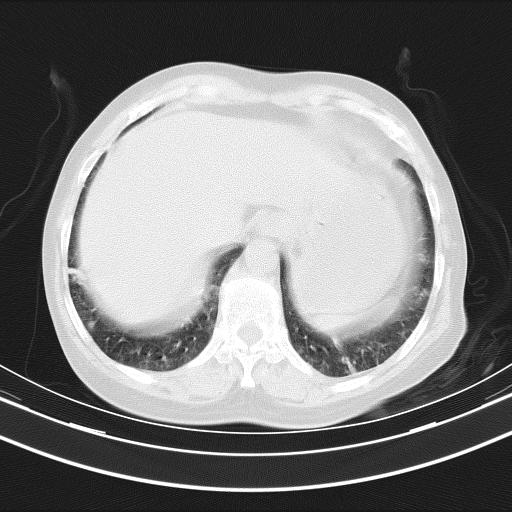

老年女性,嗜睡3天,意识模糊。轻咳,无发热。

两肺慢支炎伴感染,左侧胸腔积液。纵膈及双侧肺门淋巴结肿大建议复查。

双肺多发淡片影,毛玻璃影,,支持支气管肺炎,,建议血气找原因,,嗜睡是否肺性脑病?有没有慢支病史?

1)两肺感染性病变;建议抗炎治疗后复查。2)纵隔淋巴结肿大。3)左侧胸腔积液。